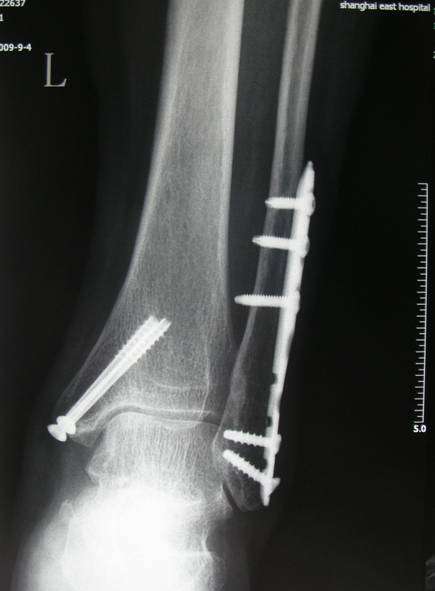

微创双踝骨折术后取内固定

图片尺寸435x591